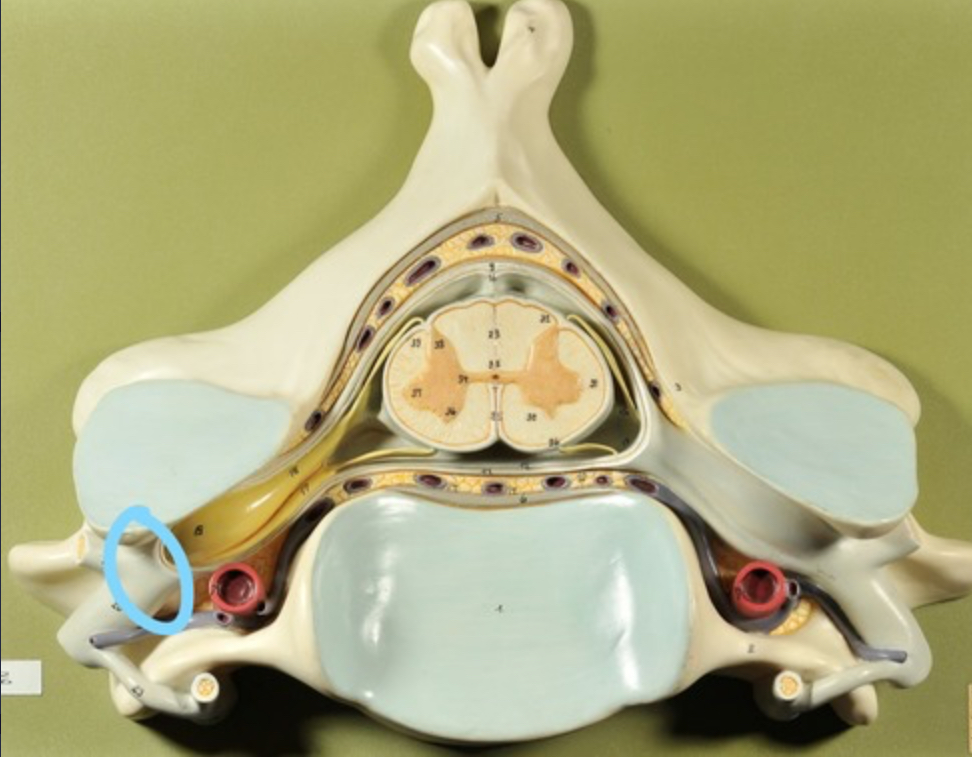

Spinal cord

Dura mater (outermost layer)

White matter of spinal cord

Gray matter of spinal cord

Ventral horns (of gray matter)

Lateral horns

Dorsal horns

Anterior columns of white matter

Lateral columns of white matter

Posterior columns of white matter

central canal of spinal cord

Pia matter

Subarachnoid space

Arachnoid matter

Subdural space (brown line)

Dura matter

Epidural space

Dorsal root ganglion

Dorsal root

Ventral root

Spinal nerve